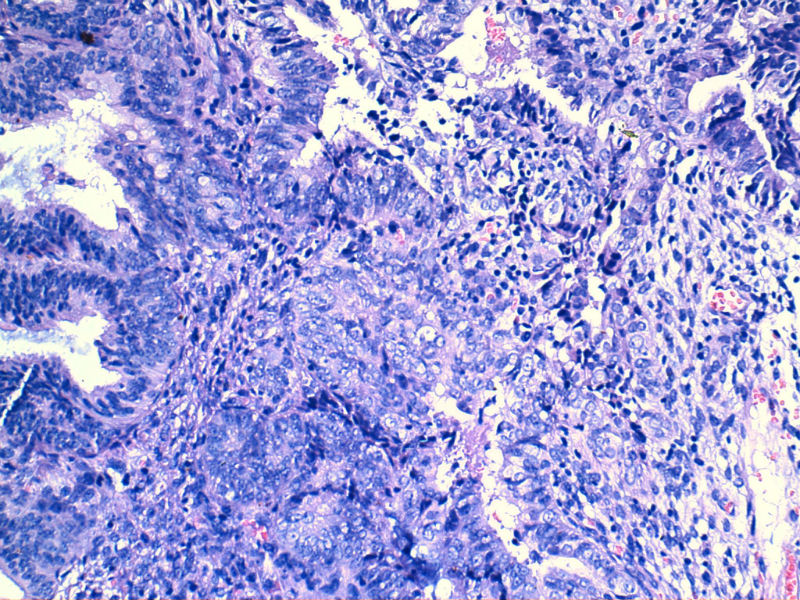

图13是做为正常对照的,图7、8、9、12显示的核大小不一,空泡状,形状不规则。女,48岁,宫血半年